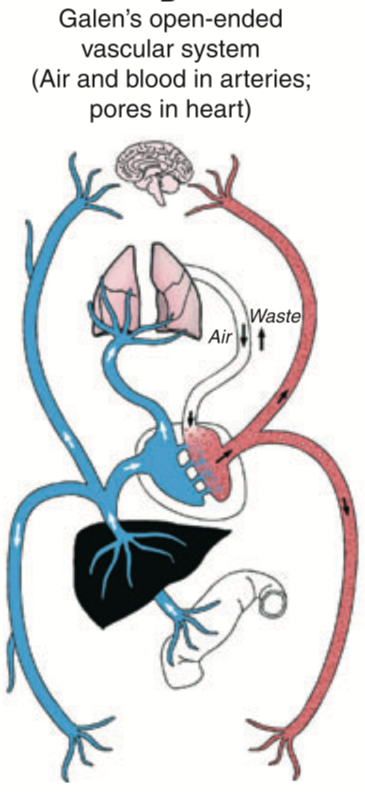

“Vesalius (1514-64), known as the modern “Father of Anatomy,” for dissecting human bodies, was fiercely assailed by the hosts of orthodoxy. Vesalius proved that Galen had been wrong in saying that the interventricular septum of the heart was permeable.

Re: Galen of Pergamon - 129-216 AD

Remarkably, western medical beliefs and theories about blood and circulation had advanced little since Galen wrote his medical textbooks in Rome 1400 years earlier.